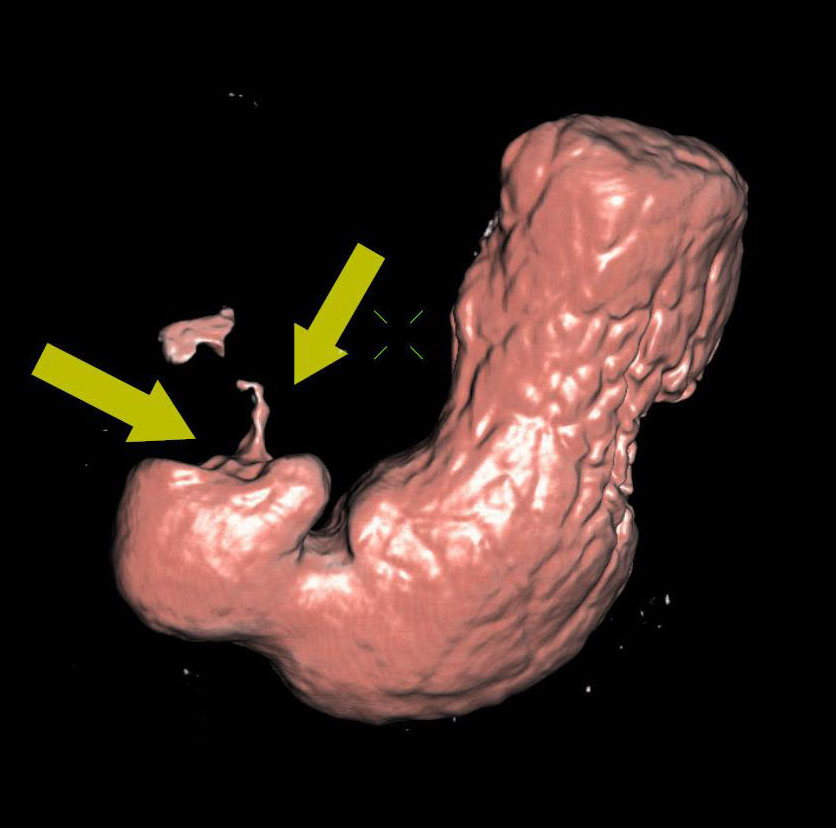

Циркулярный рак тонкой (подвздошной кишки)

Необходимо отметить, что данная патология довольно редко встречается, как правило выявляется на операционном столе у пациентов с тонкокишечной непроходимостью. На данном примере демонстрируем, что дефект кишки был диагностирован на основании 3D реконструкции, а затем уже целенаправленно подтвержден сканограммами с протяженностью процесса и степенью сужения кишечной трубки. Сыграла свою роль сопутствующая патология, которая имела место быть, а именно слабость Баугиниевой заслонки, за счёт чего тонкий кишечник полностью заполнился газом, хотя целью исследования было исключить патологию толстого кишечника.

Просвет тонкой кишки до и после дефекта в 3D-эндоскопе